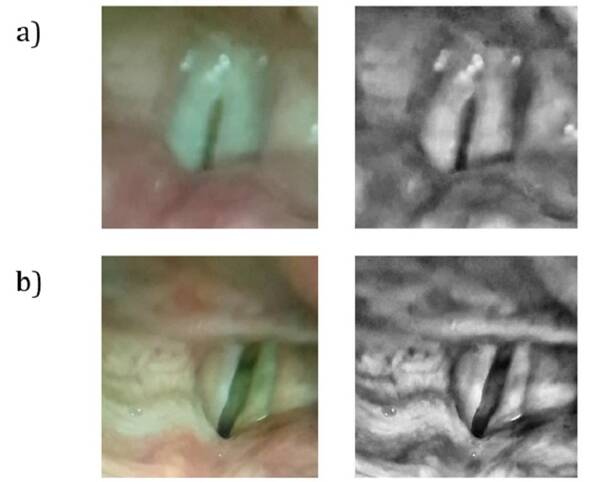

從健康(頂部)和不健康(底部)聲帶的聲帶內(nèi)部拍攝的圖像。圖片來自 JMIR Mhealth Uhealth 雜志。